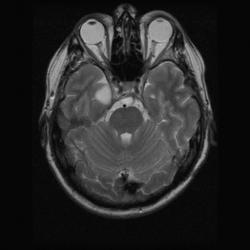

Женщина 47 лет, в течении долгого времени страдала от головных болей. В последние несколько месяцев - прогрессирующая потеря зрения (на оба глаза).

ИП FLAIR Axial

Presented images are corresponded for cerebral (right temporal-occipital region) neoplasia; high grade glioma is most suggested.

Глиальная опухоль.